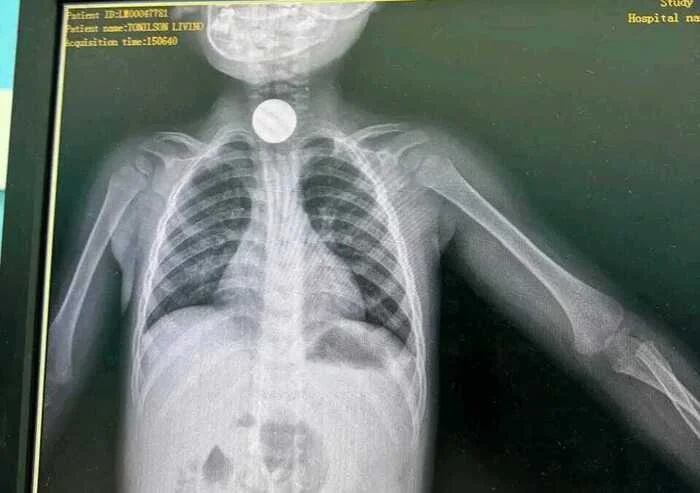

Os profissionais de saúde do Hospital Geral da Lunda-Sul realizaram com êxito uma intervenção médica que resultou na remoção de uma moeda metálica que se encontrava encravada na garganta de uma criança de seis anos de idade.

Segundo o director da unidade hospitalar, Joel Wanga Upale, o menor deu entrada na instituição em estado de risco, tendo sido prontamente atendido pela equipa médica de serviço. A intervenção decorreu sem complicações, permitindo a retirada do corpo estranho e a estabilização do paciente, salvaguardando a sua vida.